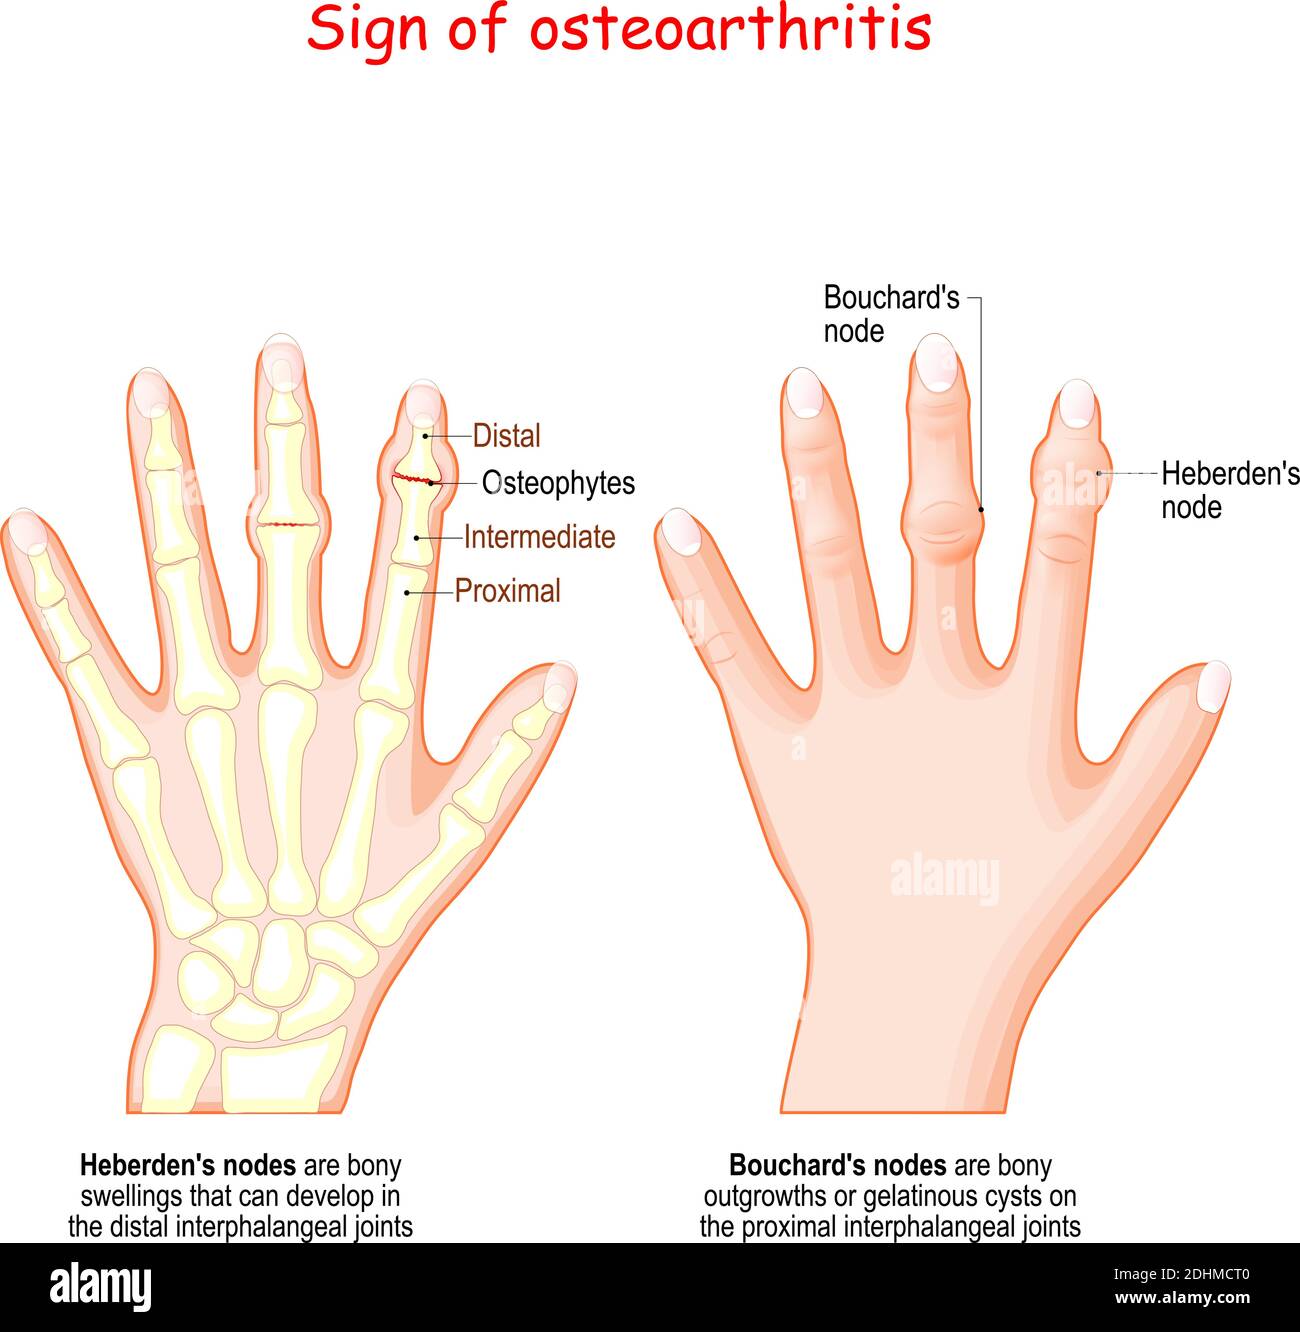

Heberden S Nodes In Osteoarthritis And Rheumatoid Arthritis

Heberden S Nodes In Osteoarthritis And Rheumatoid Arthritis

Bouchard Clipart And Illustrations

Rheumatoid Arthritis Vs Osteoarthritis Keri Leigh Biomedical Creations

Bouchard Nodes What Are They Causes Signs Symptoms And More

Osteoarthritis Stages

Osteoarthritis Stages